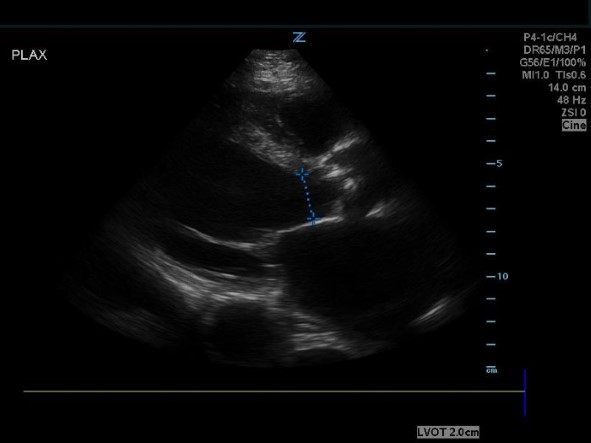

Figure 1. PLAX view showing the stenotic and calcified AV.

- Obtain a parasternal long axis (PLAX) and right ventricular outflow view (RVOT) and examine the aortic valve leaflets. Is there AV calcification? How’s the AV leaflet mobility? Is there also LV hypertrophy? Several studies have found that novice sonographers have been able to accurately pick up severe aortic stenosis.4-6

*Notice how calcified the AV leaflets are and how little the valve orifice opens.

- Obtain a PLAX and measure the LVOT cross sectional area (by measuring LVOT diameter).